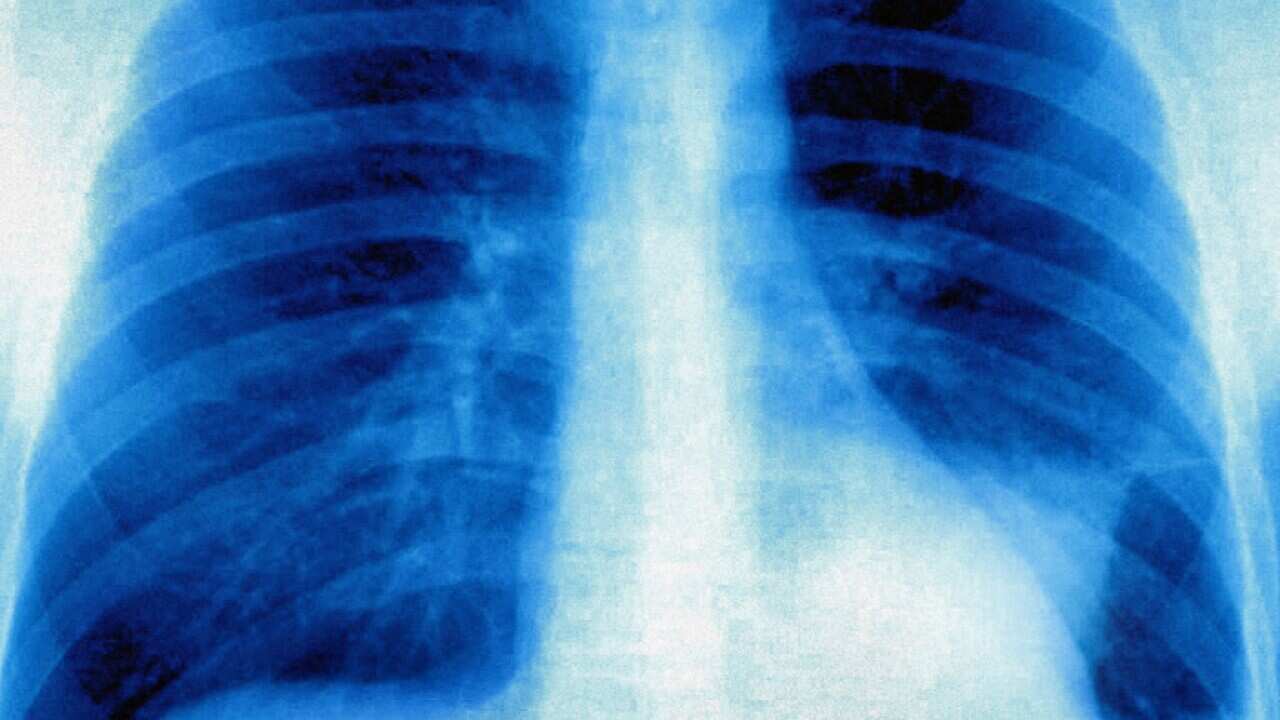

記錄內容包括很多個人資料,例如過敏反應、身體狀況、治療方法、服用藥物、以及血液等各類的測試。

澳洲有超過500萬人巳設有My Health Record,是一個個人健康狀況的綜合記錄。

My Health Record 有利的地方是可以方便醫護人員查閱,省卻以前因為資料不詳的不方便。